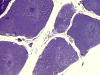

On hematoxylin-eosin stained sections, there is an increased variation of fiber diameter with many atrophic fibers intermingled with fibers of normal caliber. There is no evidence of fiber grouping or perifascicular atrophy. No inflammatory cells are present. There is also mild interstitial fibrosis (Panel A). On higher magnification, many fibers have a round concentric structure (Panel B). Irregular, centrally located depositions are also identified on modified Gomori's trichrome. The concentric nature, however, is not as obvious as in the hematoxin-eosin stained sections (Panel C). Type I and II fibers are not clearly separated in the ATPase preparation at pH 9.4. This is a common situation in chronically ill muscle (Panel D). The type I fibers are unusually dark. There is an increase in the proportion of type I fibers. The atrophic fibers are usually type II fibers. The concentric lesions are found predominantly in type I fibers (Panel E). There is an increase in PAS staining which is consistent with increased glycogen storage (Panel F). No increase in lipid content is demonstrated by oil red O (Panel G). On NADH-TR reaction, the concentric structures appear to have a clear central core that is devoid of enzymatic activity, a rim with intense enzymatic activity and a surround zone with relatively normal reactivity. These features are classic for target fibers (Panel H and I). No deficiency of laminin-2 (merosin) (Panel J) or dystrophin (Panel K) is demonstrated by immunohistochemistry. The central lesions are also immunoreactive for both laminin-2 and dystrophin. Immunohistochemistry for desmin demonstrate a core of strong immunoreactivity and also strong reaction in the sarcoplasmic membrane (Panel L and M). The target structures are also well demonstrated on semithin sections (Panel N). On electron microscopy, z-disc streaming is a common finding and they are often admixed with a substantial amount of dense granular electron dense substance (Panel O and P). There are also numerous cytoplasmic bodies characterized by radiating intermediate filaments (spheroid bodies) (Panel Q and R).

Pathology

The two major pathologic findings are inclusion bodies and granulofilamentous material. Type I fibers are predominantly affected. Inclusions are eosinophilic on hematoxylin-eosin stain and bluish on modified Gomori’s trichrome stain. These inclusions are often negative for oxidative enzymes. A strong reactivity for desmin can be demonstrated by immunohistochemistry. The abnormal accumulation can occur as cytoplasmic inclusions, subsarcolemmal inclusions, spheroid bodies (10-20 mm oval or spherical inclusions), and patches or “hyaline structures”. In some cases, there is Z-disc streaming but no masses are demonstrated by trichrome stain. Numerous negative areas may be demonstrated by oxidative enzyme reactions. An accentuated intermyofibrillar network is seen by antidesmin antibody staining. Under the electron microscope, spheroid bodies appear as cytoplasmic bodies with a dense, granular core surrounded by fine filaments in a coronary arrangement. Although they are conspicuous on light microscopy, they may not be as distinctive at the ultrastructural level.